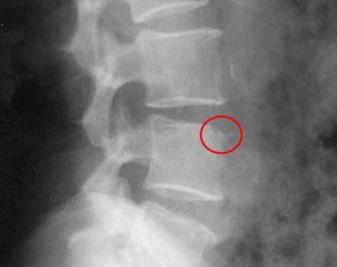

Confirman el diagnóstico pues detectan un pericardio engrosado, con frecuencia calcificado, las imágenes de elección son: la tomografía o resonancia magnética (cabe resaltar el diagnóstico diferencial con la miocardiopatía restrictiva).

Las pruebas de imagen TRATAMIENTO

La pericardiectomía (mortalidad operatoria del 7-10 %) es la única opción de tratamiento definitivo para los pacientes con pericarditis constrictiva crónica, que tienen síntomas persistentes y prominentes.